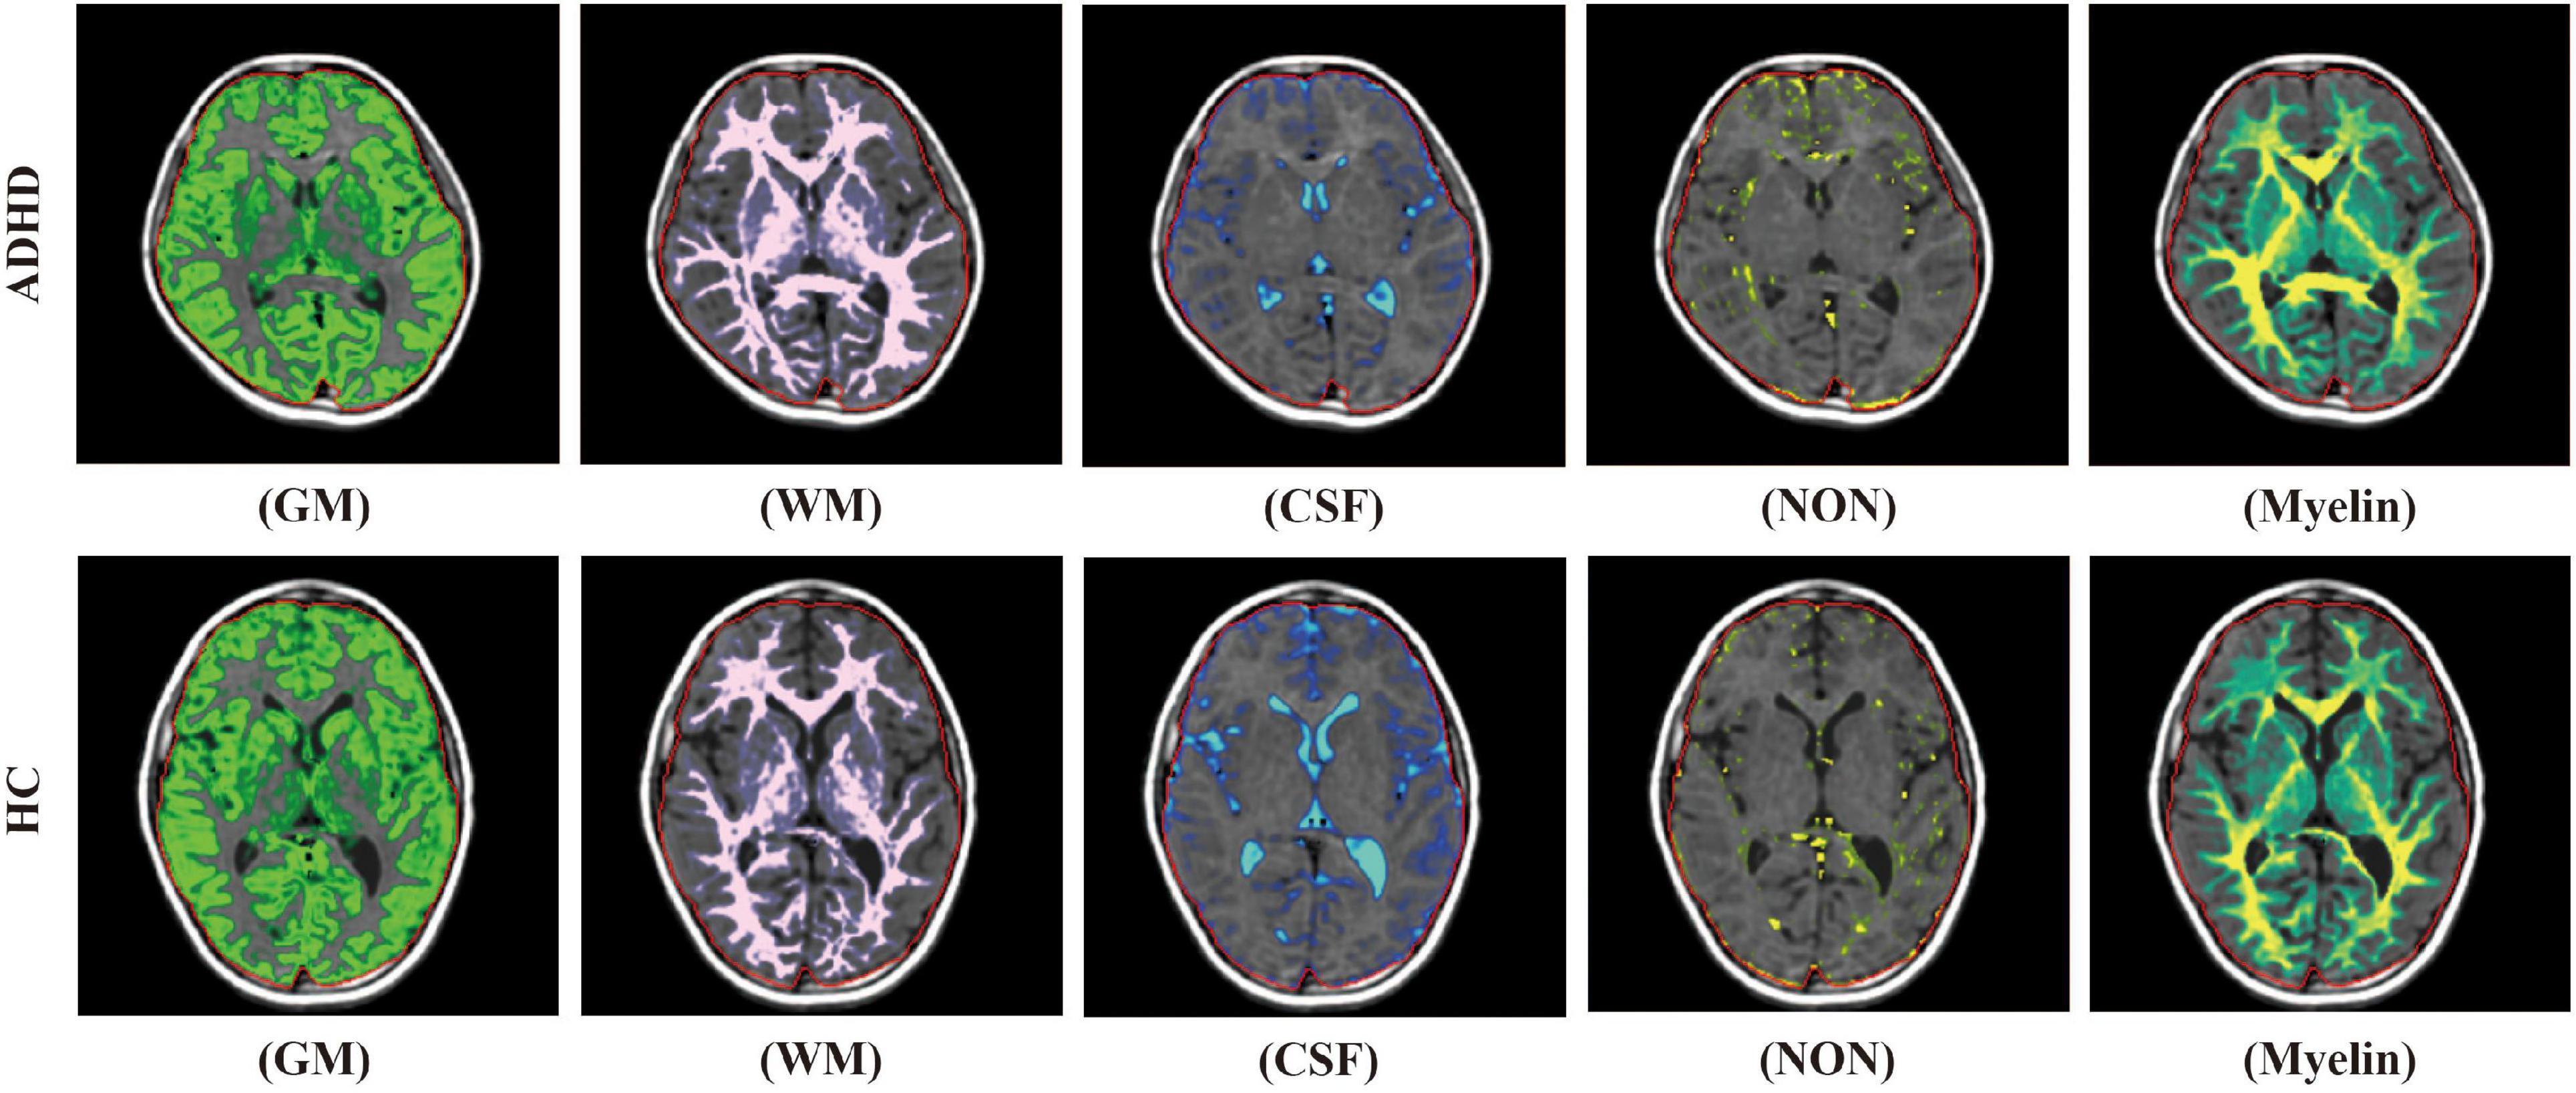

ADHD Brain Vs Normal Brain Functions Differences More

ADHD Brain Differences Stuff4Educators

Adhd Vs Normal Brain Brain Patterns Put Adhd In Focus Australasian

Brain Markers Of ADHD Identified In Children s MRI Scans